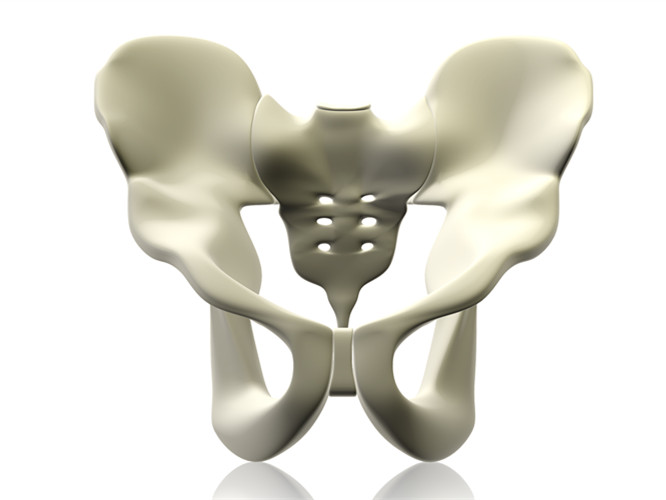

正常的耻骨(就是大腿根中间的骨头),是靠耻骨韧带连接在一起的,所以叫「耻骨联合」。

女性怀孕的时候,尤其是在分娩前,随着胎头慢慢下降进入骨盆,卵巢会分泌出一种叫“松弛素”的物质,使得骶髂关节、耻骨联合软骨及韧带变得松弛,耻骨联合及两侧骶髂关节出现轻度分离,从而使得骨盆出现暂时性的扩大,以利于宝宝的顺利娩出。

在分娩的过程中,由于胎儿过大、产程过长、急产、难产、产时用力不当或姿势不正确等,都会进一步导致耻骨联合过度分离再加上由于产后腰部过于劳累、受寒等因素,引起耻骨联合韧带的损伤,致使骶髂关节发生细微错位,耻骨联合位置在产后仍不能恢复到正常位置而形成产后耻骨联合分离症。